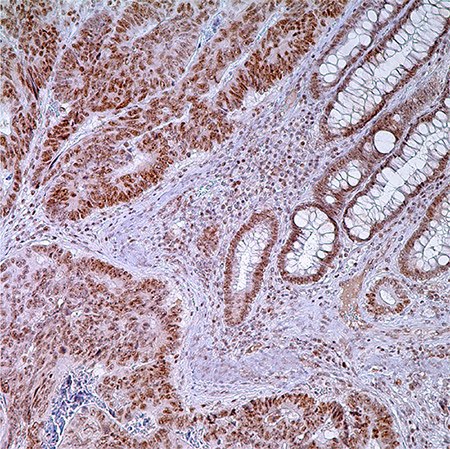

Figure 1. PMS2 (EPR3947†) - adenocarcinoma of colon. Note nuclear labeling of adenocarcinoma cells, normal crypt cells, and lymphocytes in lamina propria.